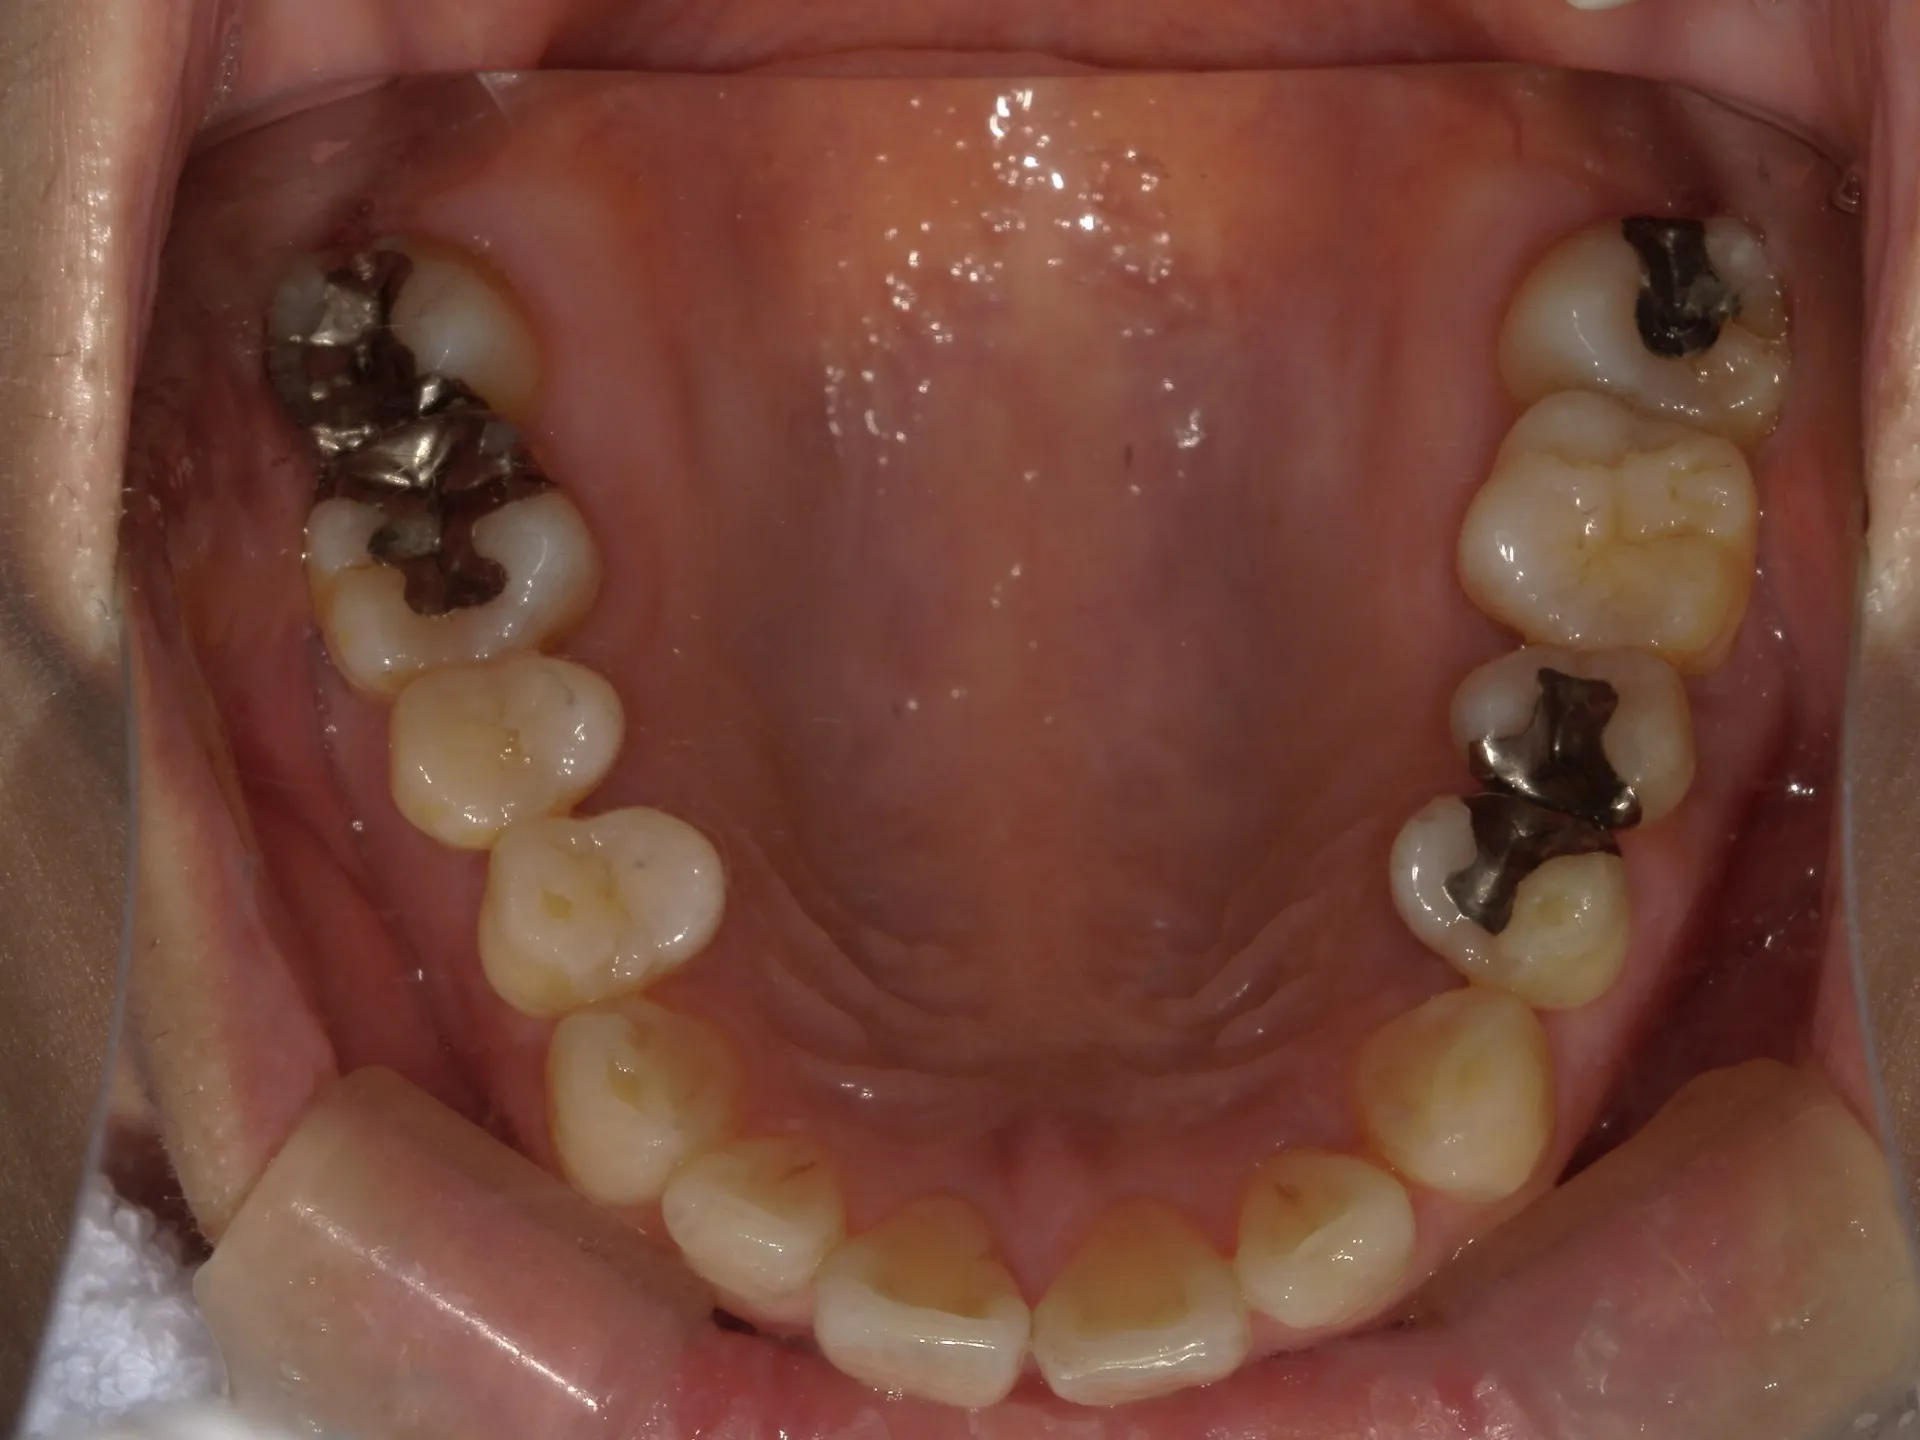

当院では矯正治療と歯周治療を平行して行うことにより矯正治療を進めていけることができました。

しかしながら、今回の治療途中で歯茎が腫れるなどの影響もあり、歯周治療中の矯正治療はリスクであることは患者様にも初回の段階で説明していることもあり、患者様もこの状態の歯並びで満足しており、歯を残すためにも今回は矯正治療を中断する希望をされました。